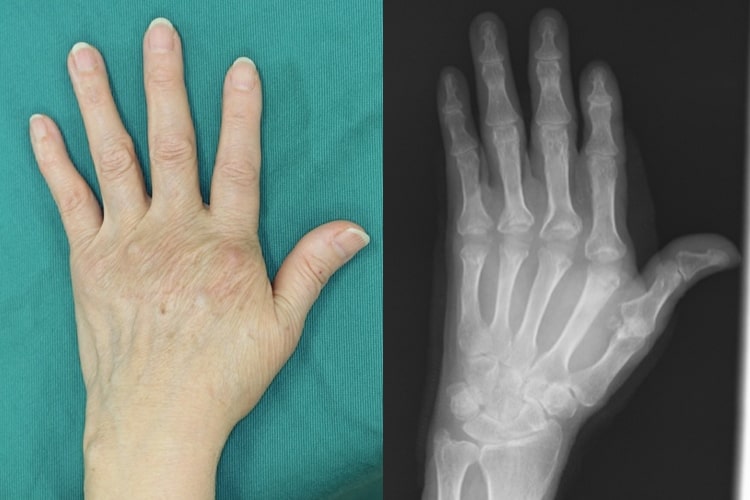

リウマチ術前写真

術前

リウマチ術後写真

人工指関節置換術後

関節リウマチにより手や指、肘の関節が破壊されて変形や疼痛が生じます。滑膜炎により指の腱が切れてしまうこともあります。関節リウマチの治療の基本は内服加療ですが、骨破壊が生じてしまったり、腱が断裂した場合は手術が必要です。

手や指、肘の変形、痛み、腫れが出現します。突然指が伸びなくなったりすることもあります。

腱が切れた場合は腱移行や腱移植を行って治療します。手の腫れや痛みが持続した場合、関節破壊の程度に合わせて滑膜切除、関節形成、関節固定を追加します。最近は人工手関節置換術を行う場合もあります。指や肘の関節リウマチについても、腫れや痛みが持続する場合は人工関節置換術を行うことで生活レベルの向上が期待できます。